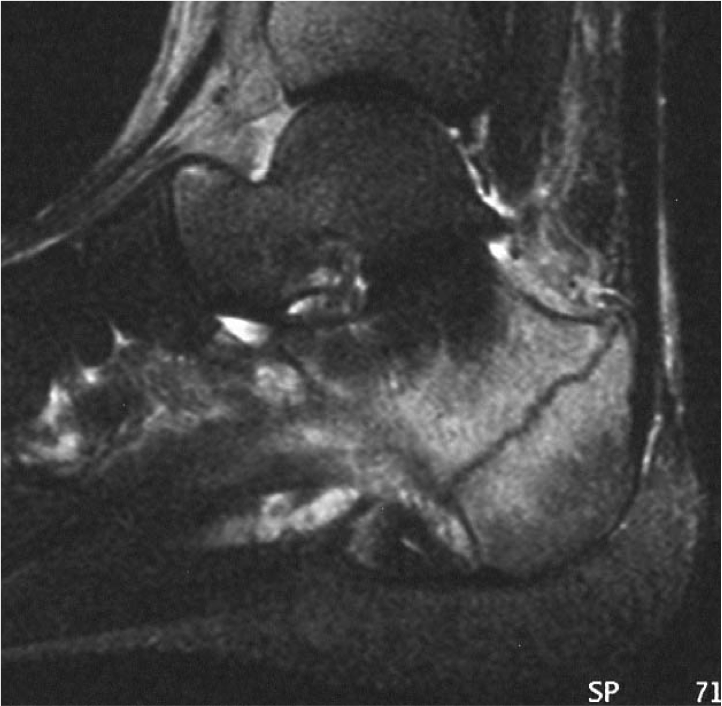

-les liquides: le liquide céphalo rachidien sur une coupe du cerveau (=liquide qui baigne le cerveau, donc en gros c'est la couleur du cerveau quoi), le liquide synovial dans une articulation...

-la corticale des os: c'est un milieu complètement exempt d'eau. Il sera donc en hyposignal dans les pondération rho